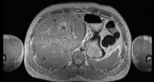

Visible Human male: Sectio transversalis 1531

CT

NMR

Pd                          / T2 \                         T1